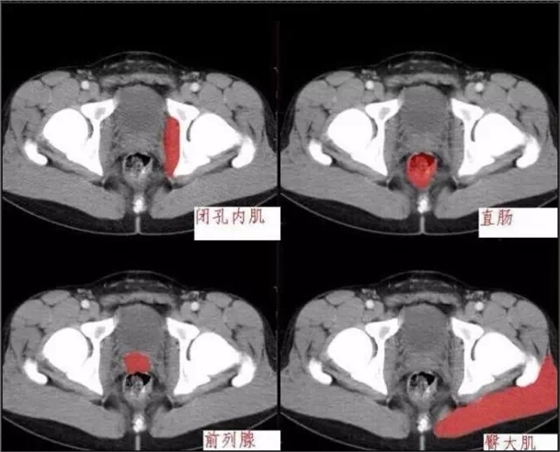

640.webp (2).jpg

640.webp (3).jpg